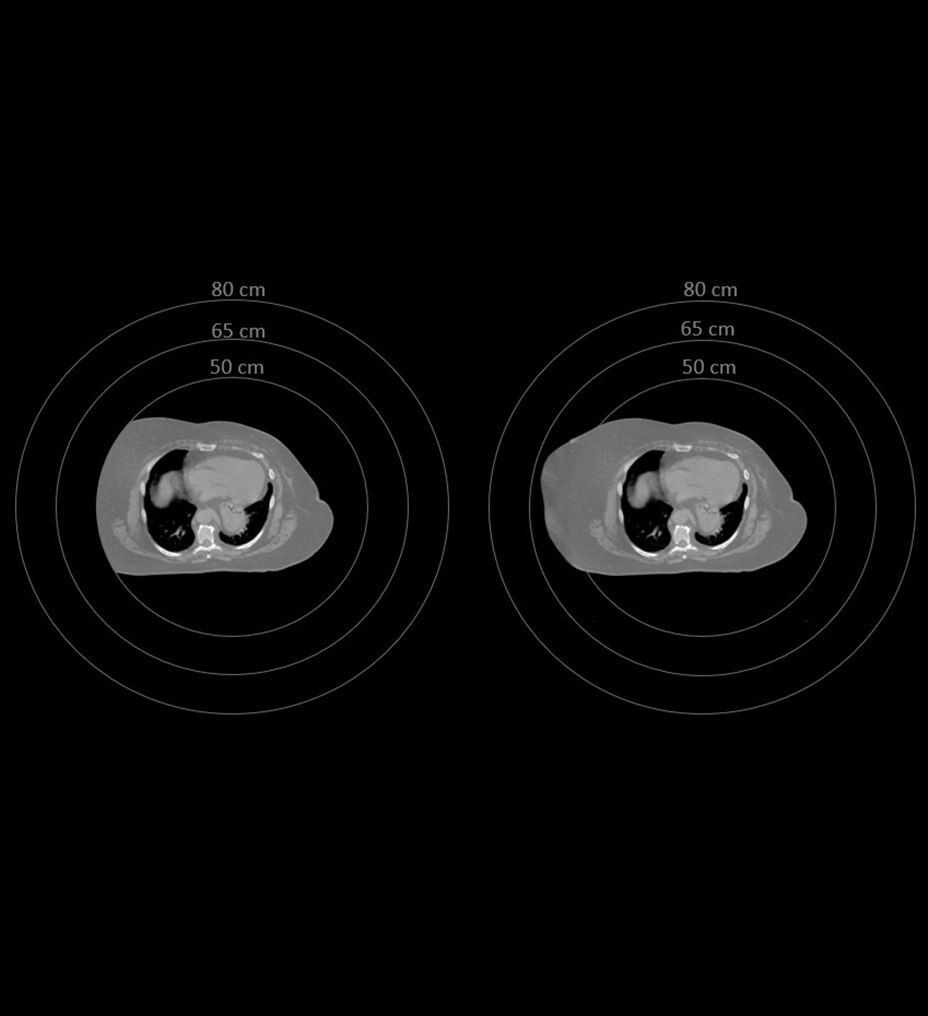

Les besoins de la radio-oncologie sont uniques. Il est donc important d’obtenir des données d’image sur l’intégralité du tunnel à partir du simulateur CT. MaxFOV2 utilise l’algorithme d’apprentissage profond exclusif de GE HealthCare pour créer une vue détaillée jusqu’à 80 cm.

Avec le champ d’exploration d’affichage (DFOV) étendu jusqu’à 80 cm

, MaxFOV2 offre moins de limitations et une meilleure qualité d’image, notamment :

• Précision de la surface de la peau de ± 2 mm et précision de la densité scanographique de l’eau à ± 40 HU avec DFOV* de 50 cm à 70 cm

• Précision de la surface de la peau de ± 3 mm et précision de la densité scanographique de l’eau à ± 60 HU avec FOV* de 70 cm à 80 cm

* Comme démontré lors des tests avec fantôme